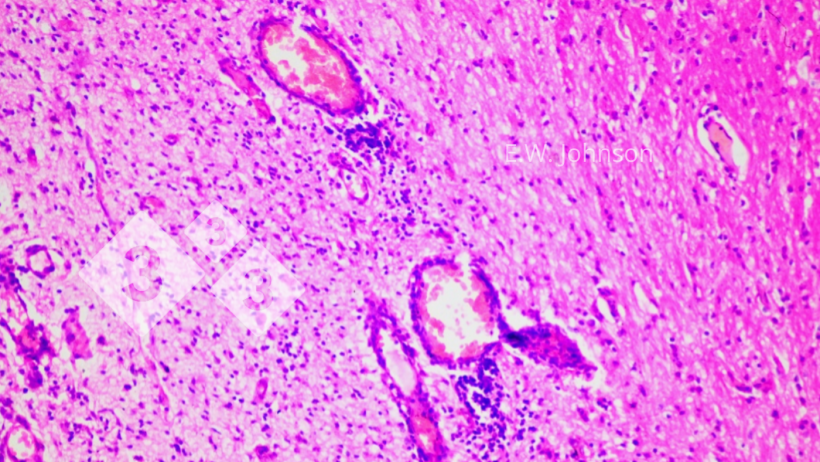

En dehors de la lésion oculaire, aucune lésion macroscopique n'est observée par le personnel de l'élevage. Le liquide intra-orbitaire aspiré des yeux semble clair et normal. Le frottis de liquide oculaire coloré au Giemsa révèle quelques cellules mononucléaires et quelques bactéries en forme de bâtonnets (bacilles). Quelques Escherichia coli sans particularité sont isolés du liquide oculaire. La possibilité d'une cause bactérienne est écartée. Les échantillons de ganglions lymphatiques, de cerveau et de foie fixés au formol sont traités par une méthode rapide d'inclusion en paraffine pour obtenir des sections de tissus qui sont colorées à l'hématoxyline et à l'éosine (H&E).

Image 2. Manchons périvasculaires et gliose. Cerveau.

L'examen microscopique du cerveau révèle une méningoencéphalite avec des manchons périvasculaires et une gliose (image 2) et une infiltration des méninges par des cellules inflammatoires mixtes mononucléaires et polymorphonucléaires (image 3). Image 3. Méningite avec des cellules mononucléaires et quelques cellules polymorphonucléaires. Cerveau.